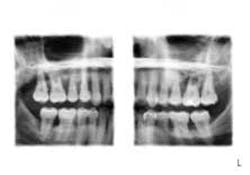

• True Extraoral Super Bitewing Program — A high-resolution detailed image of all posterior teeth with separated interproximal contacts, no overlap — all within eight seconds.

• Interproximal Panorex Program — A high-resolution panoramic image that limits the interproximal contact overlap.

• The Smart Pan — Nine selectable layers with a 1 mm shift from one panoramic exposure. This limits patient positioning errors during exposure.

Planmeca is the only company with SCARA technology that provides the diagnosing capability to perform these programs. Traditionally, panorex machines have an X-ray head that rotates on one single axis around the patient’s head, therefore giving us tooth overlap. Planmeca has a multi-jointed robotic arm that enables free geometry-based image formation. The arm can produce any movement pattern required to allow for a wide variety of imaging programs. No matter who your patient is, the diagnosing process has now been streamlined into seconds for your office staff. They will not be asking you to leave a patient to help them get a radiograph on a difficult patient. Having the right technology makes practicing dentistry easier and more cost-effective. In our practice, we assist many of our referring practitioners by taking diagnostic radiographs for their difficult patients so they can diagnose and treatment plan accordingly.